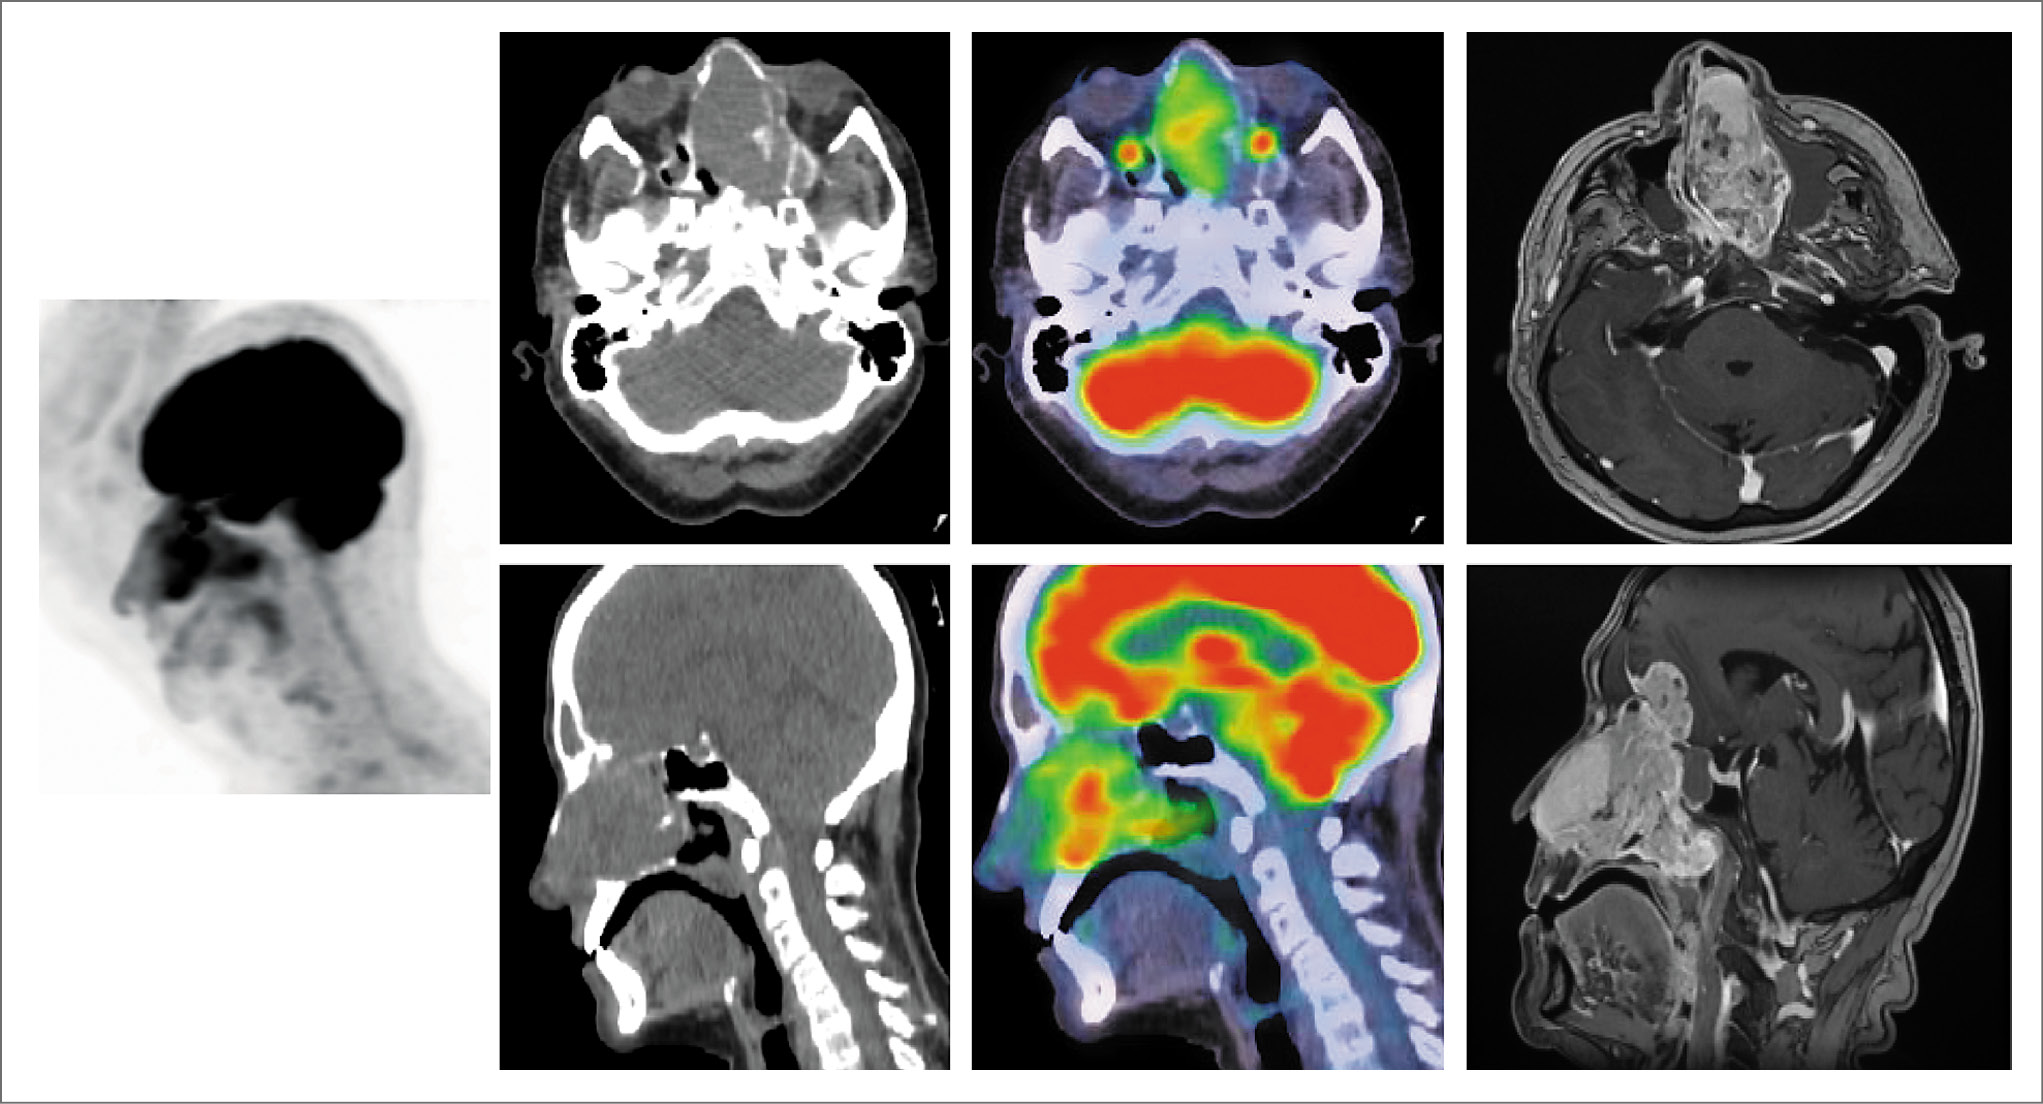

Выполнена ПЭТ/КТ. В полости носа и носоглотке, клетках решетчатого лабиринта определяется объемное образование мягкотканной плотности с нечеткими границами размером 85×38×73 мм, SUVmax 4,22. Отмечается деструкция медиальной стенки левой глазницы и левой верхнечелюстной пазухи, клеток решетчатого лабиринта, перегородки носа, носовых раковин. Опухоль распространяется через решетчатую пластинку в переднюю черепную ямку, с компрессией базальных отделов лобных долей головного мозга. Признаков бремени болезни в других органах и системах не выявлено (рис. 2).

Рис. 2. Пациентка М., 67 лет. На MIP ПЭТ, аксиальных и сагиттальных КТ и ПЭТ/КТ проекциях в полости носа слева и носоглотке, клетках решетчатого лабиринта определяется объемное образование мягкотканной плотности, с фиксацией РФП, размером 85×38×73 мм. Отмечается нечеткость контуров медиальной стенки левой глазницы и левой верхнечелюстной пазухи, клеток решетчатого лабиринта, перегородки носа, носовых раковин (деструкция). Образование распространяется в переднюю черепную ямку через решетчатую пластинку.

На основании изложенного установлен диагноз: эстезионейробластома T3N0M0, стадия С по Kadish. Назначена лучевая терапия на первичную опухоль.

Проведена лучевая терапия на первичную опухоль, суммарная очаговая доза (СОД) 66 Гр.

Через 8 нед с целью оценки эффекта проведенной терапии выполнена ПЭТ/КТ с 18F-фтордезоксиглюкозой. В полости носа сохраняется объемное образование неправильной формы с четкими неровными контурами размером до 51×31×50 мм (ранее 83×38×77 мм) с повышенным поглощением ФДГ SUVmax 3,81 (ранее SUVmax 4,22), с распространением на ячейки решетчатой кости, носоглотку и переднюю черепную ямку. Медиальная стенка левой глазницы истончена, с нечеткими контурами. Глазные яблоки, зрительные нервы и ретробульбарные пространства не изменены. Эффект расценен как частичная регрессия опухоли (рис. 3).

Рис. 3. Пациентка М., 67 лет. Через 8 нед по окончании лучевой терапии, СОД 66 Гр. Частичная регрессия опухоли. На MIP ПЭТ, ПЭТ/КТ на аксиальных и сагиттальных КТ и ПЭТ/КТ проекциях в полости носа сохраняется объемное образование неправильной формы, с четкими неровными контурами, размером до 51×31×50 мм, с гиперметаболизмом ФДГ SUVmax 3,81, с распространением на ячейки решетчатой кости, носоглотку и переднюю черепную ямку.